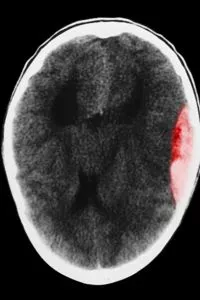

AVC

Notre établissement dispose d’un programme d’éducation thérapeutique « la vie après l’AVC ».

Un accident vasculaire cérébral ou AVC, communément appelé « attaque cérébrale », est une perte soudaine d'une ou plusieurs fonctions du cerveau.

Il est provoqué :

par un arrêt brutal de la circulation sanguine à l'intérieur du cerveau. C'est l'accident vasculaire cérébral ischémique. L'arrêt de la circulation du sang dans une artère ne permet plus un apport suffisant en oxygène et en éléments nutritifs . Cela entraîne la mort des cellules cérébrales, au niveau de la zone du cerveau touchée : c'est l'infarctus cérébral ;

ou par la survenue d'une hémorragie intracérébrale. C'est l'AVC hémorragique.

La gravité de l'accident vasculaire cérébral dépend de la localisation et de l'étendue des zones cérébrales touchées.